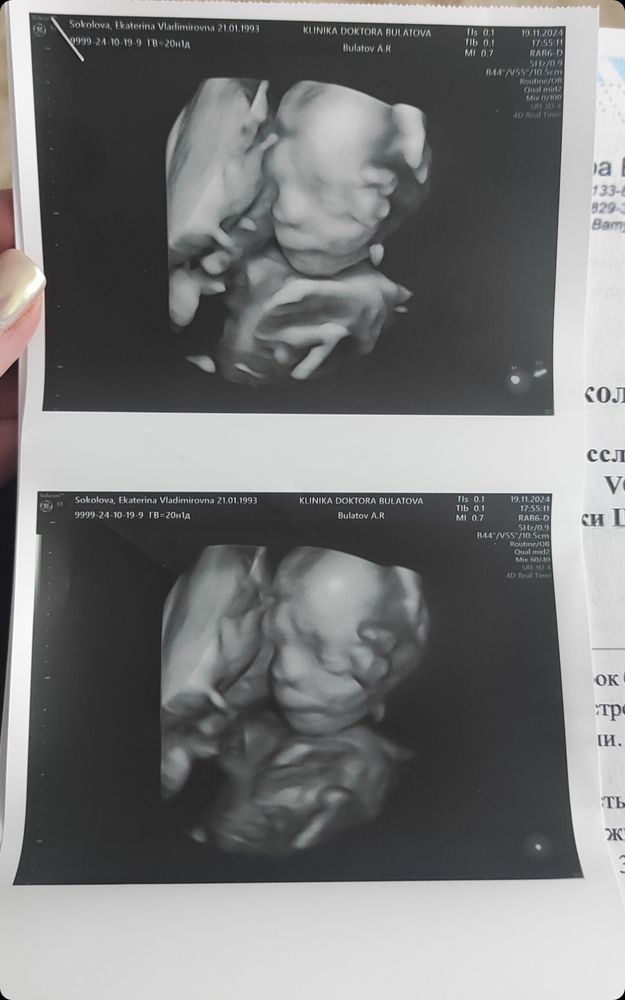

Изображение Изображение Изображение

Александра, там на фото написаны сроки, 2 фото - 37н 1, 3 фото - 39н 1 На первом фото к сожалению нет информации, но думаю месяц 3-4

20 недель. Изображение До этого недель в 17 делала, тоже было неплохо видно уже. Если будете делать, просите видео записать, так здорово его потом пересматривать 😁